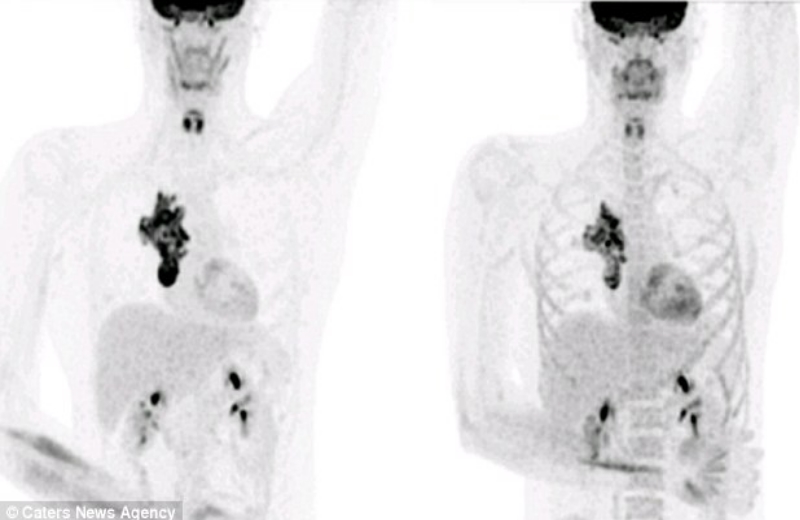

Agora o paciente linfoma, considerado terminal, compartilha incríveis fotos digitalizadas do encolhimento do tumor.

Agora, nove meses após o início do tratamento – que incluiu uma combinação de drogas e um transplante de células-tronco da irmã dele – o câncer praticamente desapareceu.

Na verdade, os médicos disseram que o tumor agora é tão pequeno que parece em remissão.

Key Eastwood, que é ex-estudante de mecânica, disse: “Depois de ver meus exames eu não podia acreditar como estava grande o tumor no meu peito”.

Veja as radiografias e a redução: